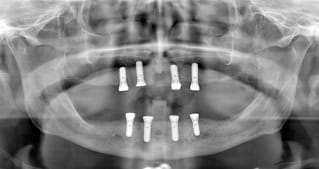

8 devraient suffire ,non?

8 en haut tu veux dire...avec 2 sinus lift...et un grand bridge transvissé de 16 à 26 par exemple???

quand je dis 8, c'est huit pour le haut et le bas.

complet haut amovible sur deux barres (donc 4 implants en haut) ou sur 4 locators (y en a qui ont déjà fait ?)

Le All-on-four en haut avec des Locators n'est pas une bonne solutions. En bas, c'est mieux.

L'os du maxillaire étant peu résistant, un désign sur 6, voir 8 implants est nettement mieux, avec barre ou fixe selon le nombre d'implants, la longueur, le diamêtre, la densité osseuse, l'occlusion, la forme du patient, l'arcade opposée, bref, il y a plusieurs facteurs.

mais 4 implants devraient suffire pour réhabiliter le bas et éviter définitivement le partiel.

si le patient à le budget pour 4 implants en haut alors ok pour éliminer une partie du palais.

pour les amateurs de ALL ON FOUR, il faut savoir que les résultats ne sont pas aussi favorables que cela et que c'est évidemment très dépendant de l'antagoniste. ici, c'est pas envisageable (enfin, me semble t'il).

proposition d'un all on 6 ou de sinus-litf bilatéral avec 8 implants et fixe.